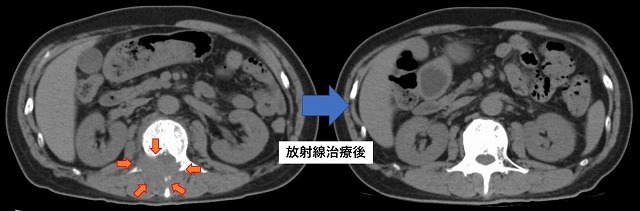

手術で取り残す可能性が高い箇所を中心にIMRTで照射。

胃や小腸、腎臓など周囲の臓器を避けて照射している。